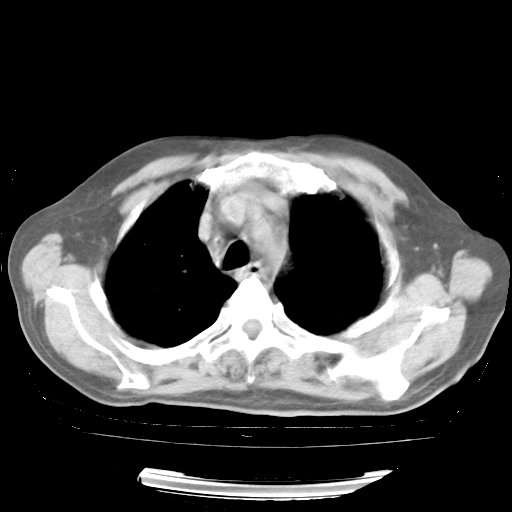

4月28日肺部CT——再次出现类似去年5月9日——透光度降低,“间质性”改变。

个人阅读4.14日肺部CT平扫:纵隔窗无异常,但肺窗示:双下肺内、后基底段有片絮状侵润影,部位以后基底段为著,以间质改变为主,呈急性肺泡炎征像,和首次住院影像学有相似之处。仅是个人读片,明日请相关专家再读片哈。其它建议同上。